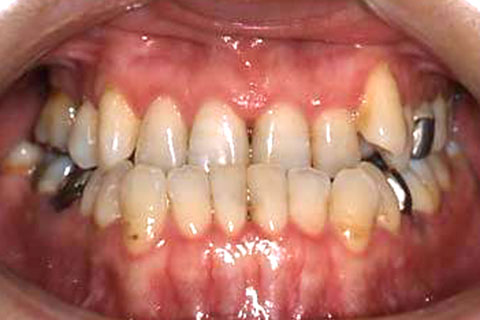

受け口(反対咬合)の症状

下あごが上あごより突出しているか、上あごが下あごより後退している状態で、咬み合わせが逆になっているので反対咬合ともいいます。お子様の場合、受け口(反対咬合)を放置していると、成長期において下あごが過大に成長し悪化しますので、出来る限り早い時期に治療することをおすすめします。受け口(反対咬合)は見た目の問題だけでなく顎の動きを制限し、将来的に顎の痛み(顎関節症)を引き起こす場合があります。また、お子様の場合は、正常な上顎の成長を阻害する可能性があります。

受け口(反対咬合)の症例